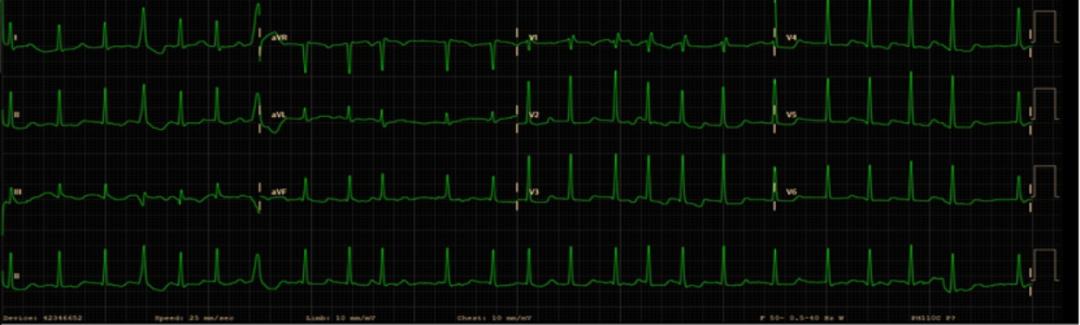

入院时查体显示:心率145次/分,血压171/91 mmHg,未闻及湿性或干性啰音,心律不齐,第一心音强弱不等,无颈静脉扩张或外周水肿。患者没有出现双手震颤、焦虑、出汗、皮肤变化或发热,她否认食欲亢进、体重减轻、失眠等不适。心电图(图1)显示心房颤动伴快速心室率。

图1 心电图这种情况第一时间当然想起我们的“神药”,给予胺碘酮150mg+20ml葡萄糖注射液(静脉推注),接着微量泵泵入转复窦律,比索洛尔和地高辛片控制心室率等治疗。